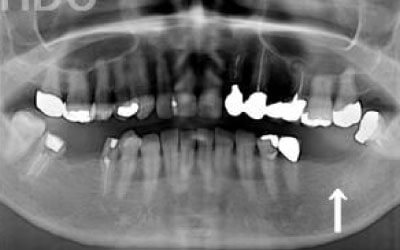

歯科の統計データをお伝えします。インプラントは、10年後に90~95%の確率で残ります。

対して、ブリッジは10年後に30~35%の確率で残っていると言われています。

ブリッジが失敗する場合、ほとんどが支えとなっている歯がダメになり、その結果抜歯が必要になることが多いです。

最も大きな違いは、前後の歯の寿命に影響が出ることです。

ブリッジの場合、抜けた歯の前後にある歯を、重度の虫歯と同じくらいまで削る必要があります。

また、抜けた歯の代わりに前後の歯が力を支えるため、その歯に常に1.5倍の負荷がかかります。

ブリッジの支えの歯は、データでは10年以内に68%が抜歯になります。